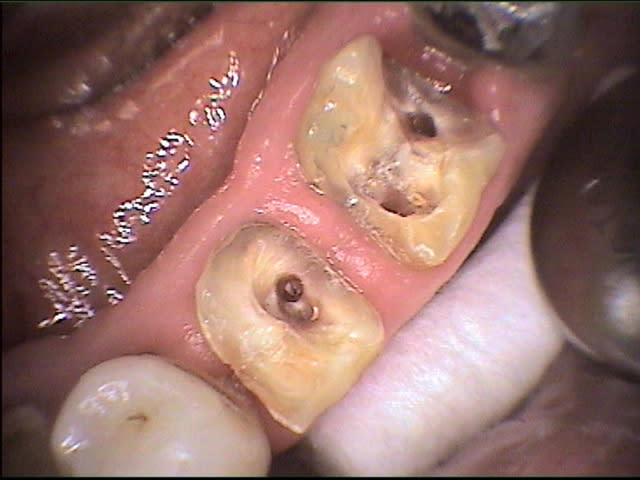

tiens, billi, qu'as-tu fait sur la 46 avec la fêlure MD?

les photos que j'ai mises sur eugenol sont extraites de mes fiches patient "DEMO" et très franchement je ne me souviens pas du cas;ma conduite en général face aux fêlures est 1-essayer de conserver 2-l'expectative ...mise sous provisoire et voir...si pas de signe clinique ou radio.. defnitif...j'aime bien les onlays métal servant de cerclage...le patient est averti;la taille de la fêlure sur la photo n'est pas très encourageante; la caméra révèle bcp de fêlures qu'on ignore